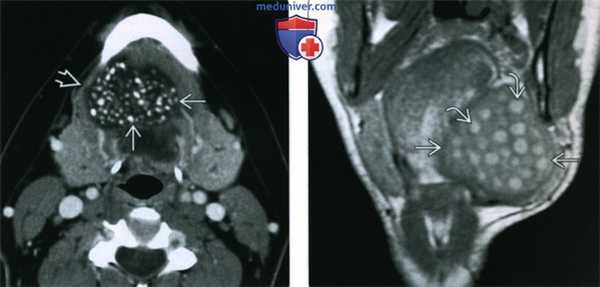

(Слева) КТ с КУ, аксиальная проекция. Располагающееся парамедианно образование подъязычного пространства. Образование имеет четкие контуры и располагается медиальнее челюстно-подъязычной мышцы. Определяются множественные кальцификаты и участки пониженной плотности, характерные для эпидермоидной кисты.

(Справа) МРТ Т1ВИ, коронарная проекция. Крупная дермоидная киста подъязычного пространства, смещающее челюстно-подъязычную мышцу в латеральную сторону. Округлые участки гиперинтенсивного сигнала представляют собой жировую клетчатку. Они характерны для дермоидной кисты и позволяют отличить ее от эпидермоидной кисты, ранулы или лимфатической мальформации.